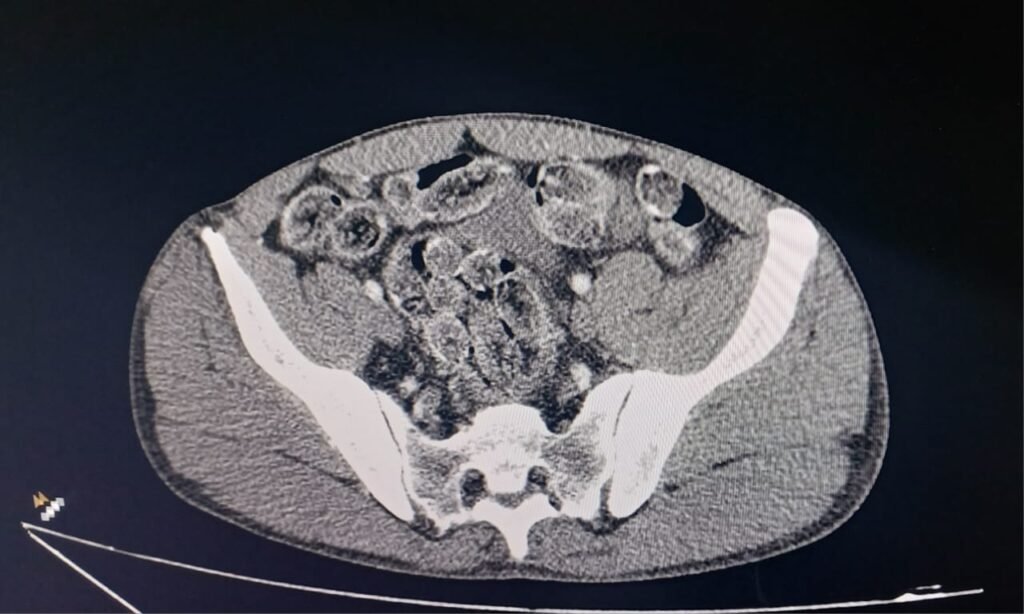

Diante da suspeita de ingestão de entorpecentes, os envolvidos foram encaminhados ao CHS (Centro Hospitalar de Sorocaba) para realização de exames médicos.

Após exames de imagem, foi constatado que os dois homens transportavam mais cápsulas de droga no interior do organismo e permaneramm internados para expelir o restante do material.